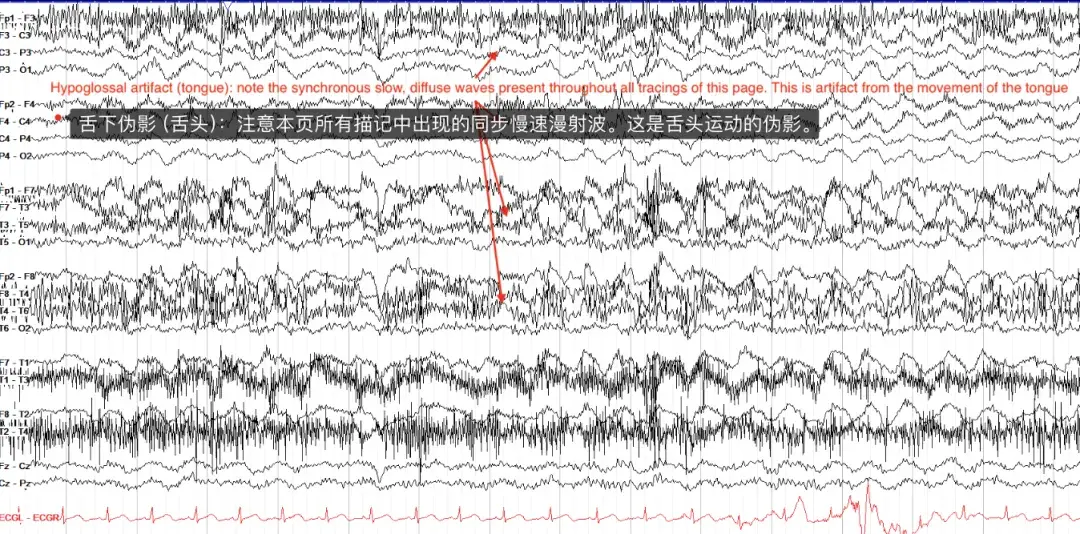

舌下伪影经常但不一定与咀嚼伪影一起出现。它由舌头的运动引起,并表现为较慢的、弥漫性的德尔塔频率活动。

注意,在下面的示例中,所有描记都具有本质上相同的运动——对于慢波睡眠之类的东西来说,这很有组织性,虽然发作模式肯定会导致这种节奏,但在这一页上没有证据表明癫痫发作特征随时间或地点的演变。

关于舌头运动伪影的一个值得注意的点是它是可重复的——你可以要求患者移动舌头,或者说“la la la”(又名舌音素),看看脑电图上是否显示出相同的模式。